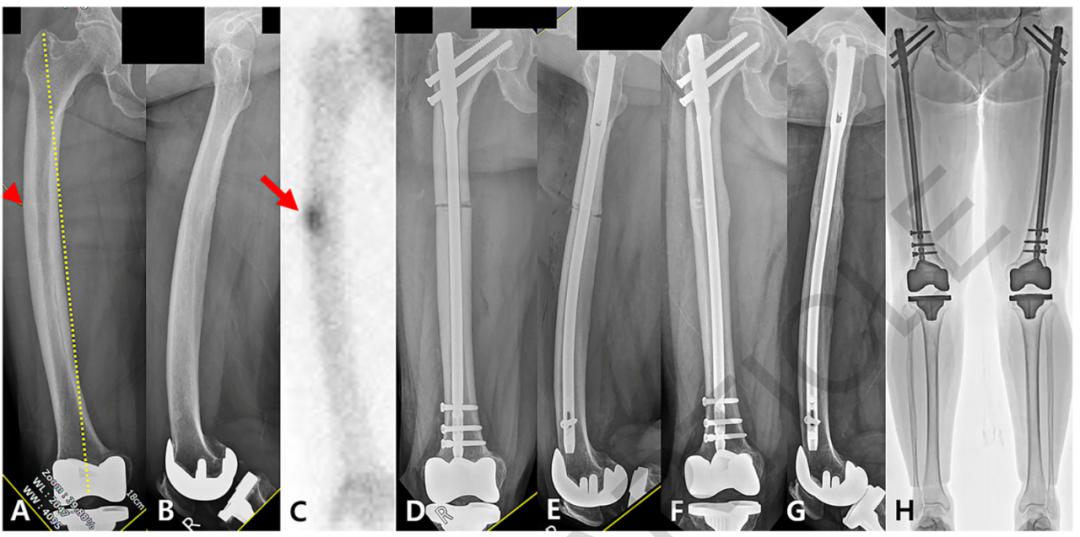

笔者团队在2010年首次提出肱骨近端解剖髓内支撑概念[8,12],并以此概念使用修整后的解剖型异体腓骨(图1)进行临床试验,腓骨支撑组随访33.5(24-48)个月,解剖腓骨支撑无头内翻与螺钉切割,总体肱骨头坏死率为10.6%,但因患者满足当前功能,均未行翻修手术,术后2年功能优良率达100%。通过形态学研究[13]分析并比较了老年和年轻患者的髓腔解剖退变模式,以更好地从解剖学上了解肱骨近端髓腔形态,完善解剖髓内支撑概念。通过有限元分析[14]对比解剖髓内支撑结构联合锁定钢板能够较锁定钢板获得更好的抗剪切与抗扭转力。为了摆脱同种异体骨资源限制,团队设计研发了髓内支撑钉与钢板系统(图2)[9],并应用于老年Neer3/4部分肱骨近端骨折,结果显示手术时间与术中出血量与单纯钢板治疗无差异,1年以上随访显示畸形愈合率11.1%远低于钢板组,Constant评分、DASH评分、患者主观优良率均高于钢板组。

图2 髓内支撑钉与钢板系统